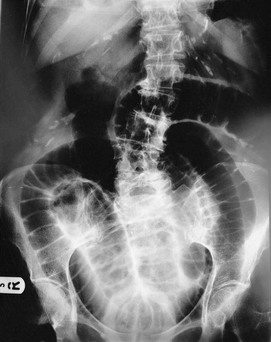

Plain abdominal radiology: Most abdominal films are taken with the patient supine. Bowel is visible when it contains gas (Figs 5.3 and 5.4); normal small bowel is less than 3 cm wide and tends to occupy the centre of the abdomen. When dilated, it shows transverse folds (plicae circulares) which completely cross the lumen. The colon usually lies peripherally and has haustrations; these folds only partly traverse the lumen (Fig. 5.3). Normal colon is less than 6 cm wide and often contains faecal lumps with a mottled appearance. Further reading about this topic is available from: http://www.studentbmj.com/topics/clinical/imaging_techniques.php.

Free intraperitoneal gas: Free gas is diagnostic of bowel perforation except after recent laparotomy. A horizontal beam chest or upper abdominal X-ray with the patient erect is the most useful method of demonstrating it as a radiolucent layer beneath the diaphragm (see Fig. 19.8, p. 275). The layer can be very small but is often obvious. Perforation can also be confidently diagnosed when the inside and outside of the bowel wall are both outlined by radiolucent shadows, but this is rare (Rigler's sign, Fig. 32.7, p. 413). Where the result is doubtful or the patient too ill to sit or stand, he or she should be placed in the right-side raised lateral decubitus position (i.e. lying on the left side) for 10 minutes. A horizontal beam X-ray taken across the table can then reveal as little as 2 ml of gas above the lateral liver border (Fig. 5.4).